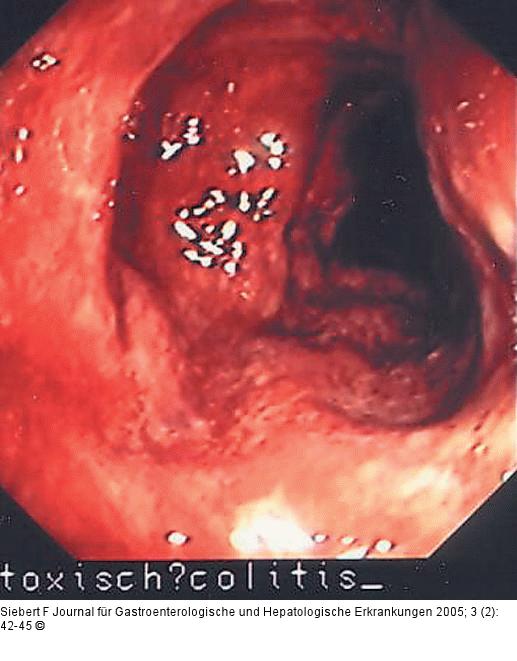

Abbildung 10a-f: Kolon - Reaktionsmuster Aphthen – Ischämisches Ulkus – Ödem, Hyperämie, Ulzeration – Zirkulär-ulzerös narbige Stenose – Pseudopolypös und narbig – Pseudomembranen (von oben nach unten) |

Abbildung 10a